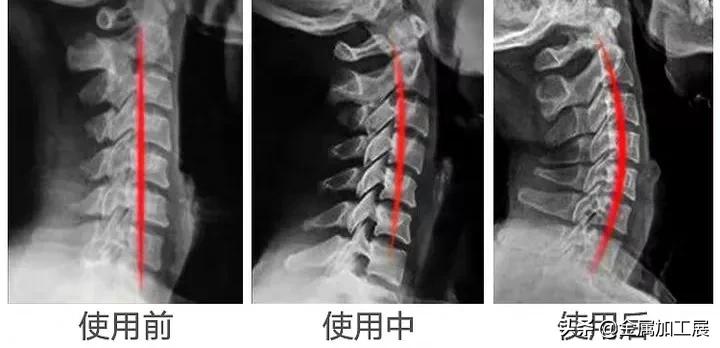

如今,有了这款日本3T颈椎牵引枕,根据人体工学打造,每天枕30分钟,就可以牵引、纠正颈椎,让颈椎恢复正常曲度。

而这款3T颈椎牵引枕,仰卧时,头部自然下垂,与牵引枕呈45°夹角,可以感觉到它与颈椎的完美贴合,不知不觉颈椎就慢慢恢复到正常曲度。

每天睡前牵引30分钟,感觉颈椎慢慢恢复到舒服的状态,脖子不再僵硬,整个人一下子轻松了不少。

它是日本骨科教授经过大量临床研究,参照颈椎生理弯曲值,通过上万名颈椎病患者试验,打造出来的。